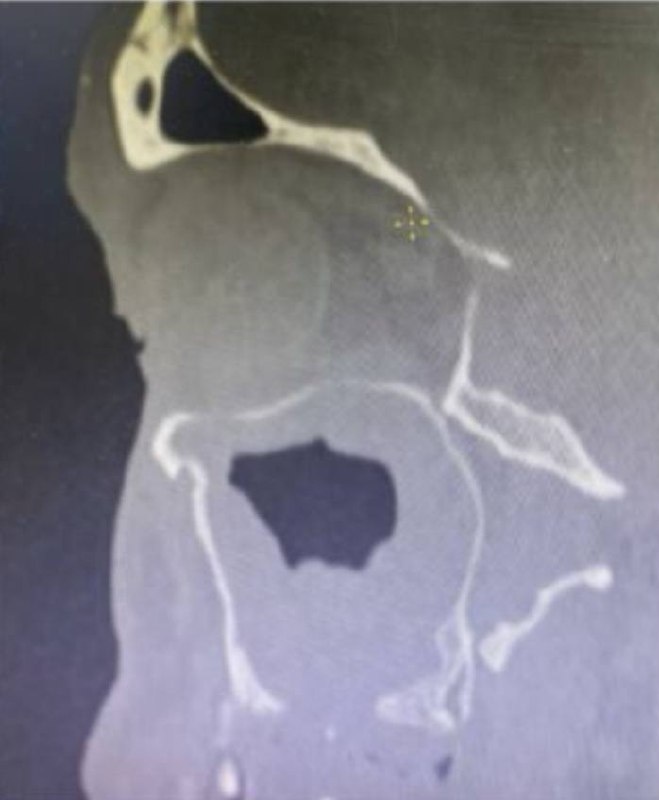

➡️По данным КТ: искривление перегородки носа, снижение пневматизации левой верхнечелюстной пазухи, сoncha bullosa слева. Дефект нижней стенки в/ч пазухи.